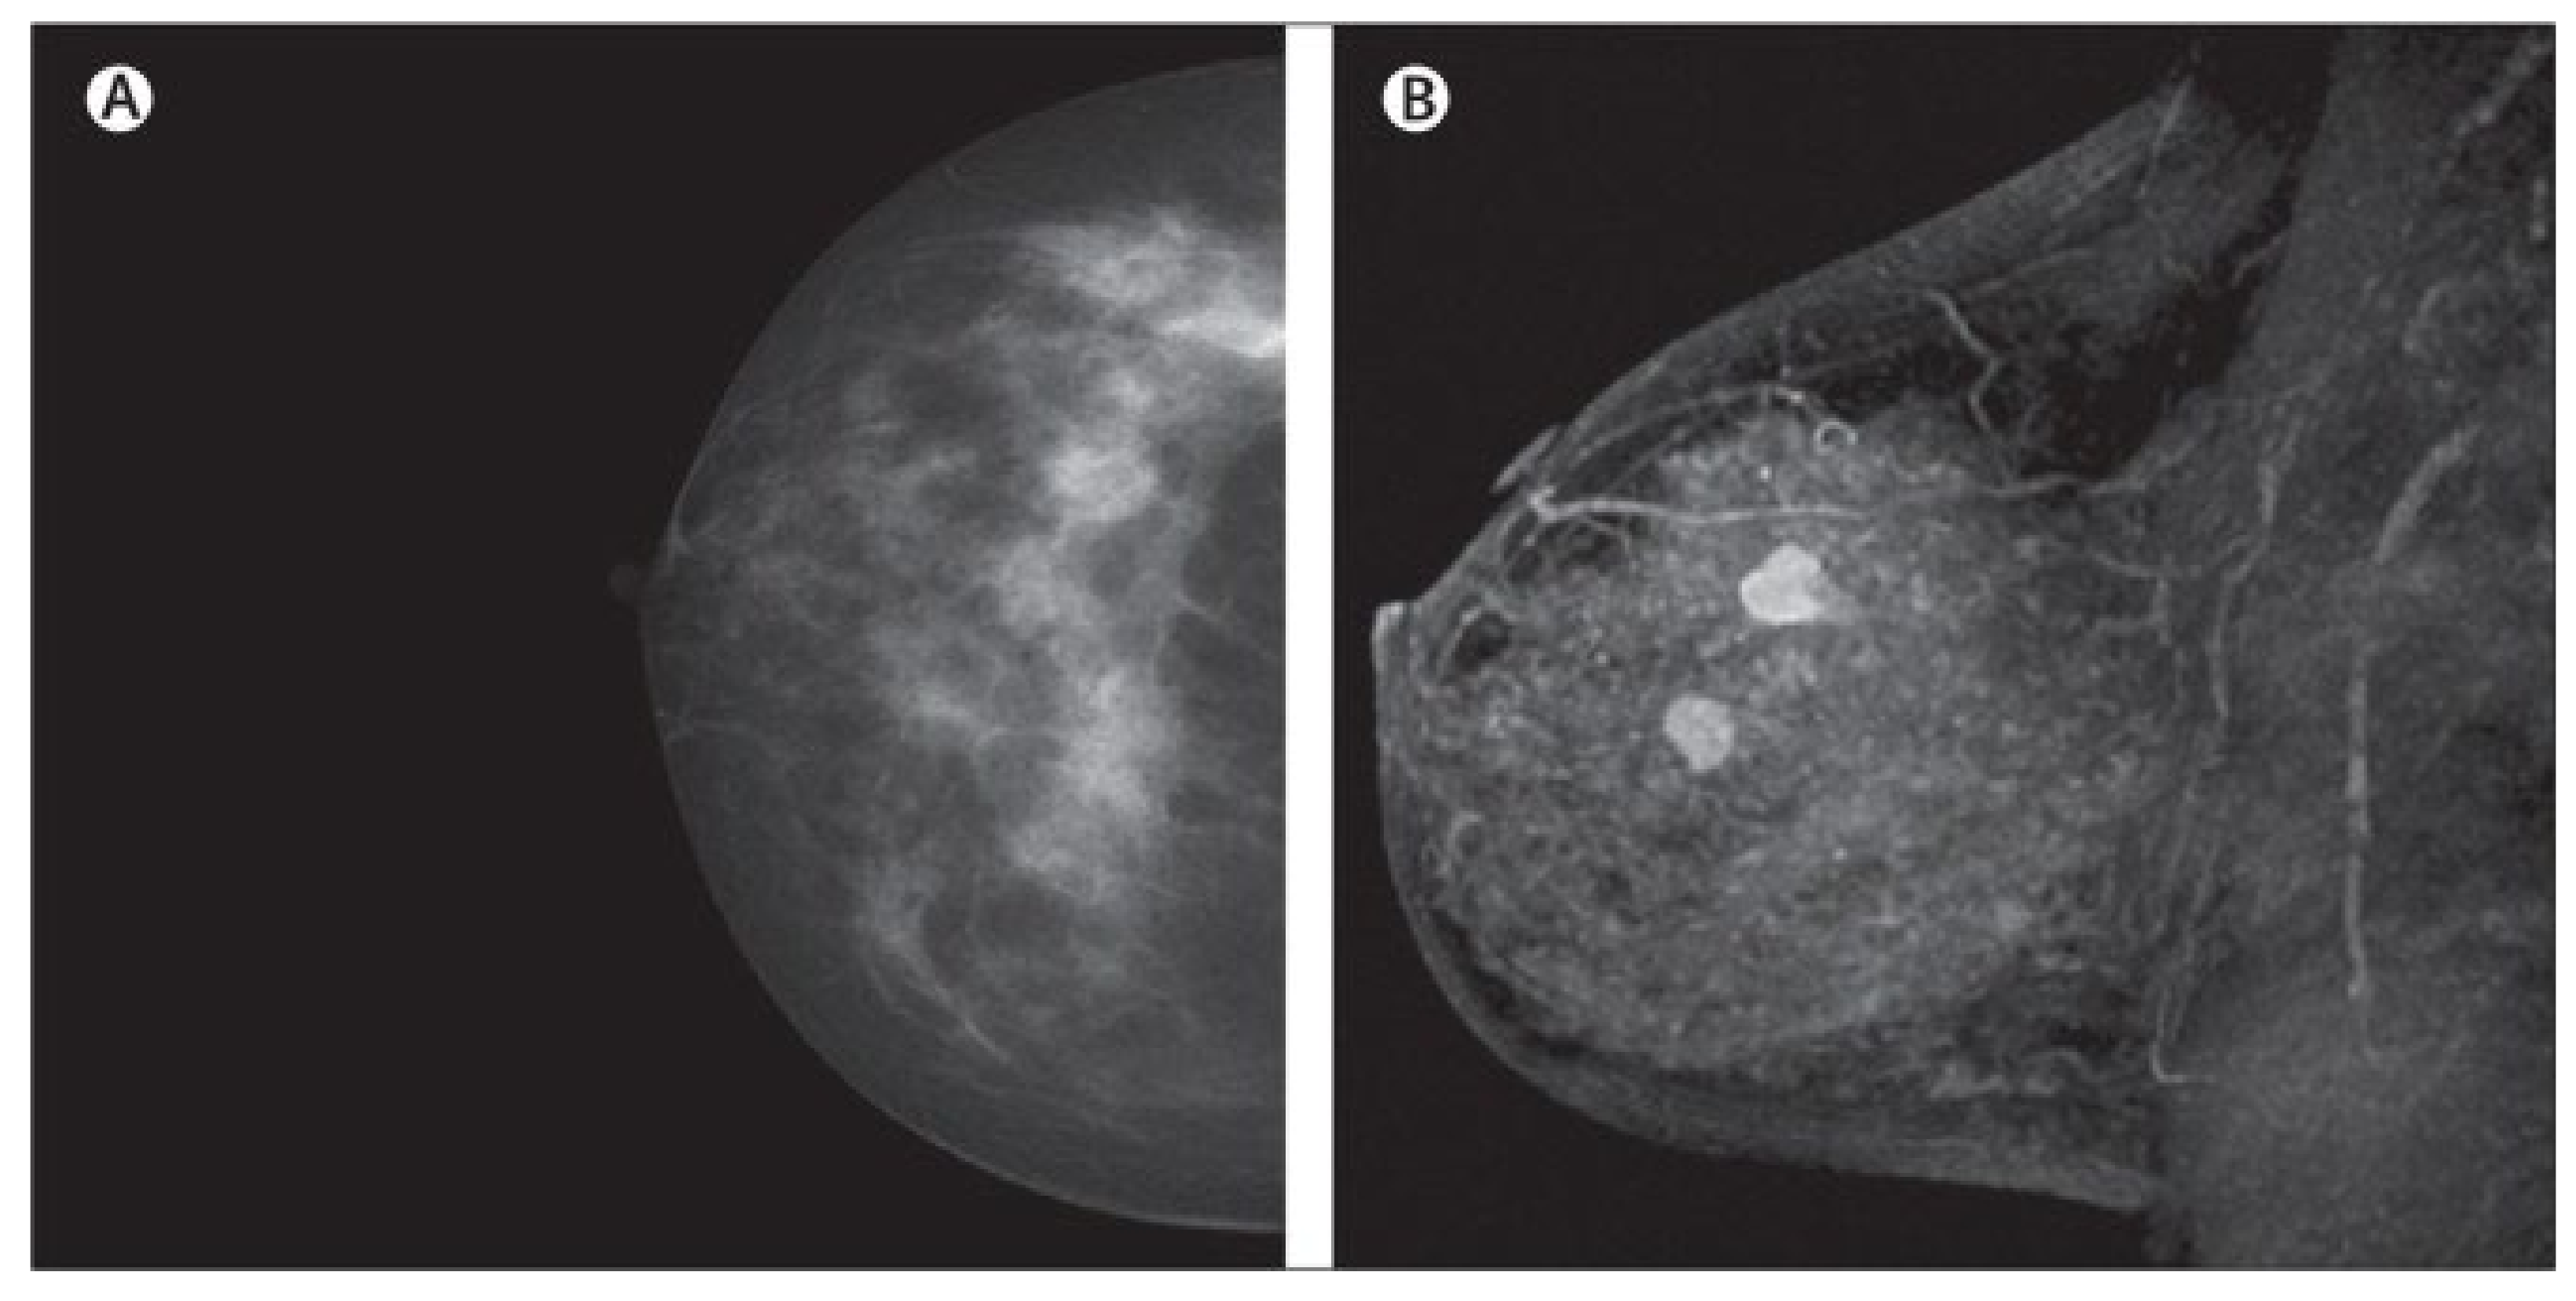

MRI creates images of the whole breast and presents it as thin slices that cover the entire breast volume. It works based on radio frequency absorption of nuclei in the existence of potent magnetic fields. MRI uses a magnetic field along with radio waves to capture multiple breast images at different angles from a tissue [81,82,83] (Figure 4). By the combination of these images together, clear and detailed images of tissues are produced. Hence, MRI creates much clearer images for breast cancer analysis than other imaging modalities [84]. For instance, the MRI image shows many details clearly, leading to easy detection of lesions that are considered benign in other imaging modalities. Additionally, MRI is the most favorable method for breast cancer screening in women with dense breasts without any ionizing and other health risks, which we have seen in other modalities such as MMs [85,86]. Another interesting issue about MRI is its capability for producing high-quality images with a clearer view via the utilization of a contrast agent before taking MRI images [87,88]. Furthermore, MRI is more accurate than MM, DBT, and the US in evaluating residual tumors and predicting pCR [79,89], which helps clinicians to select appropriate patients for avoiding surgery after neoadjuvant chemotherapy (first-line treatment of breast cancer) when pCR is obtained [90,91]. Even though MRI exhibits promising advantages, such as high sensitivity, it shows low specificity, and it is time consuming and expensive, especially since its reading time is long [92,93]. It is worth noting that some new MRI-based methods, such as ultrafast breast MRI (UF-MRI), create much more efficient images with high screening specificity with short reading time [94,95]. Additionally, diffusion-weighted MR imaging (DWI-MRI) and dynamic contrast-enhanced MRI (DCE-MRI) provide higher volumetric resolution for better lesion visualization and lesion temporal pattern enhancement to use in breast cancer diagnosis and prognosis and correlation with genomics [53,81,96,97,98]. Details about various MRI-based methods and their pros and cons are available in Table 1.

Figure 4.

Dense cancerous breast tissue images conducted by MRI method from different angles. (A) Normal; (B) malignant [82]. Reprinted/adapted with permission from [82]. 2011, Elsevier.